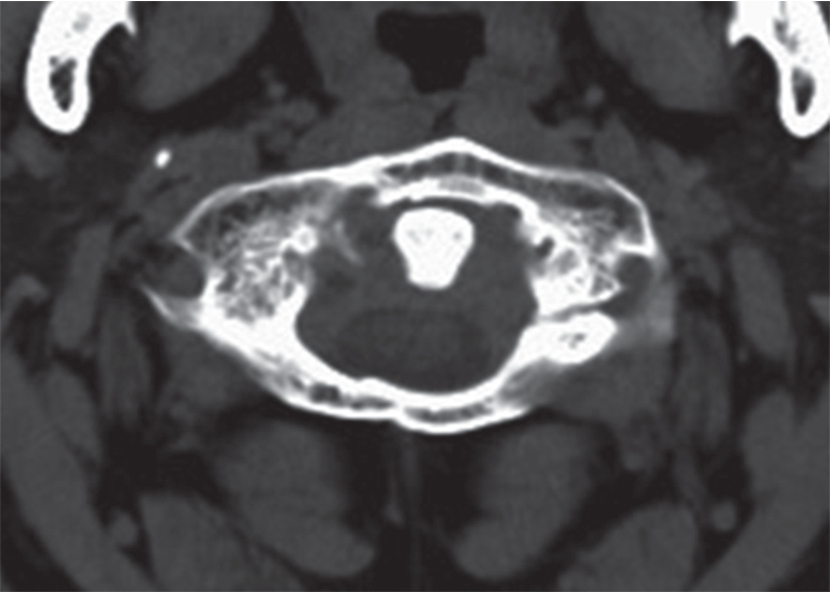

(3)创伤性椎间盘脱出:显示椎间盘局限性突入椎管使硬膜囊变形、脊髓移位(图7-2-15)。

图7-2-15 CT示爆裂性骨折